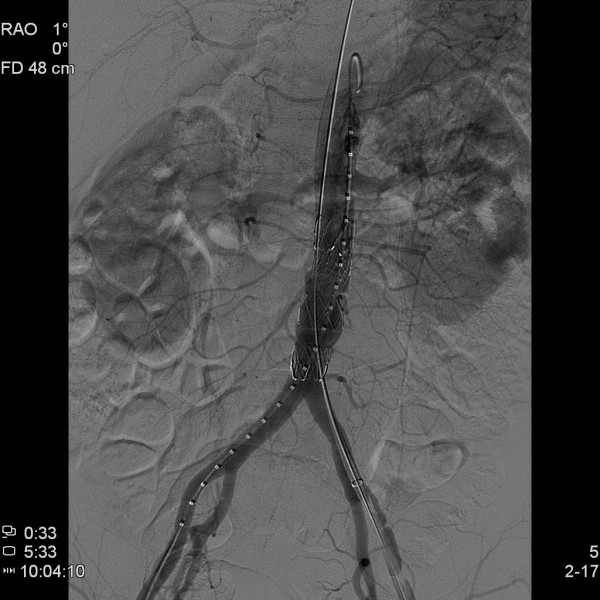

오산한국병원에서는 지난 5월 28일 오전, 제 3영상의학과 지주연 과장의 시술로 복부대동맥류 환자에 대한 스텐트 삽입술을 성공적으로 완료하였습니다.

복부대동맥류는 뱃속의 시한폭탄이라 일컬어지며 병원에 도착하기전에 사망하는 비율이 50%를 넘어가고, 살아 있어도 증상과 파열이 있는 경우에는 수술을 하더라도 성공률이 50%를 넘지 못하고 있는 실정으로 응급수술을 요하는 매우 위험한 질환입니다.

전국적으로 시술가능한 병원이 몇군데 안될 정도로 어려운 질환임에도 불구하고 이번에 복부대동맥류 스텐트 삽입술을 본 병원에서 성공하게 됨으로써 오산 및 인근지역내에 타의 추종을 불허하는 질높은 수준에 의료서비스를 제공할 수 있는 종합병원임을 다시한번 입증하게 되었습니다.